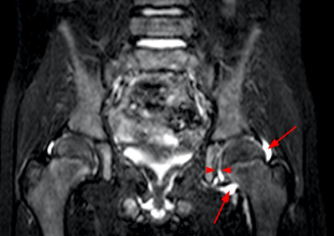

MRI: 화살표부위 밝은음영의 관절액의 증가소견